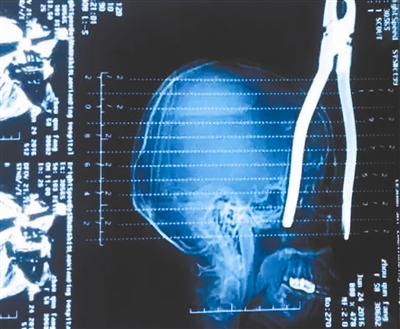

手钳把手深度插入脑部约15厘米,从颅顶贯穿眼部接近牙骨处,颅内有严重的骨折,已经出现颅内高压的情况。

25日凌晨0时,王佑芳被送进手术室做术前准备,解开包扎固定的纱布,刮掉伤口周围的头发,一把把手外裹着红色塑料层、半旧的大号手钳完整地出现在医生面前,其中一个把手插入伤者右侧脑部,外露的把手长约5厘米。

25日凌晨6时,经过三小时手术,医生将手钳从王佑芳的脑部顺利取出,随后,伤者被送到SICU(外科重症监护室)进行术后观察。刁先生告诉成都商报记者,医生在交代病情时表示,接下来的7到14天都是伤者的极度危险期,一旦出现术后感染,后果不敢想象。取出的明显半旧的手钳上,甚至还有疑似水迹,加上手钳进入脑部极深,难以进行消毒治疗,因此感染风险极大。